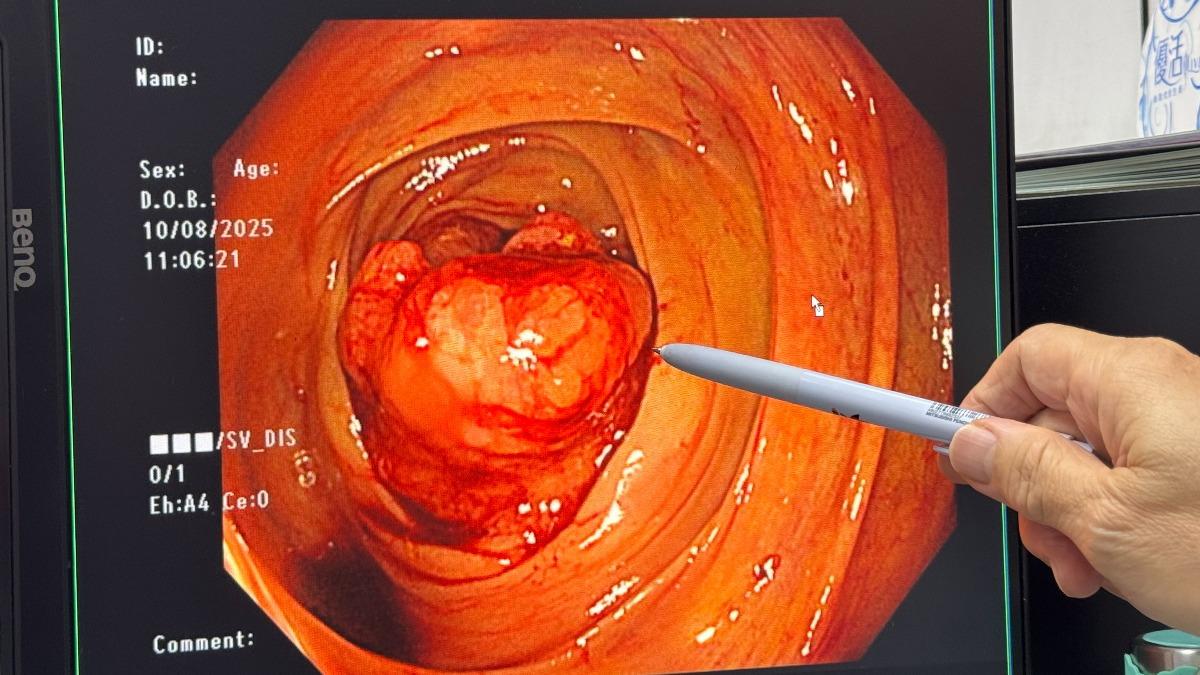

台中市一名70多歲的婦人,近日出現排便習慣、大便形狀改變,以及便中有血或黏液,甚至在家中蹲整天馬桶都沒辦法排便等異常徵兆,只是她卻不以為意,直到因身體虛弱無力,才緊急送到大甲李綜合醫院急診,未料經肝膽腸胃科醫師賴大豊檢查,在腸子內看到至少5公分大小的腫瘤,確診為大腸癌。對此,賴大豊也提醒,喜歡吃肉、燒烤,卻很少吃蔬菜水果的人,或是體重過重、過量吸菸、喝酒,以及家族病史的族群,若有不舒服症狀持續兩個禮拜,就應該要提高警覺。